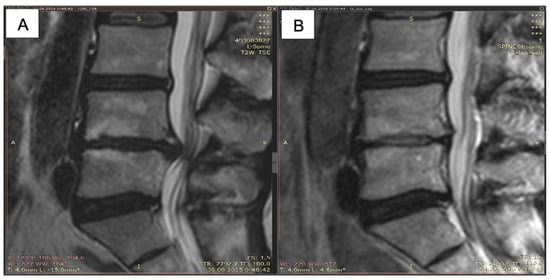

- Baskov, A.V.; Borshchenko, I.A.; Shekhter, A.B.; Baskov, V.A.; Guller, A.E.; Sobol, E.N. Long Term Clinical Results in Laser Reconstruction of Spine Discs. J. Spine 2015, 4, 210. [Google Scholar] [CrossRef]

- Borshchenko, I.; Sobol, E.; Shekhter, A.; Baskov, A.; Grin, A.; Borshchenko, M. Biological non-ablative repair of lumbar discs by transforaminal intradiscal laser irradiation: MRI quantitative analysis of the effects—Preliminary report. Lasers Med. Sci. 2020, 11. [Google Scholar] [CrossRef]